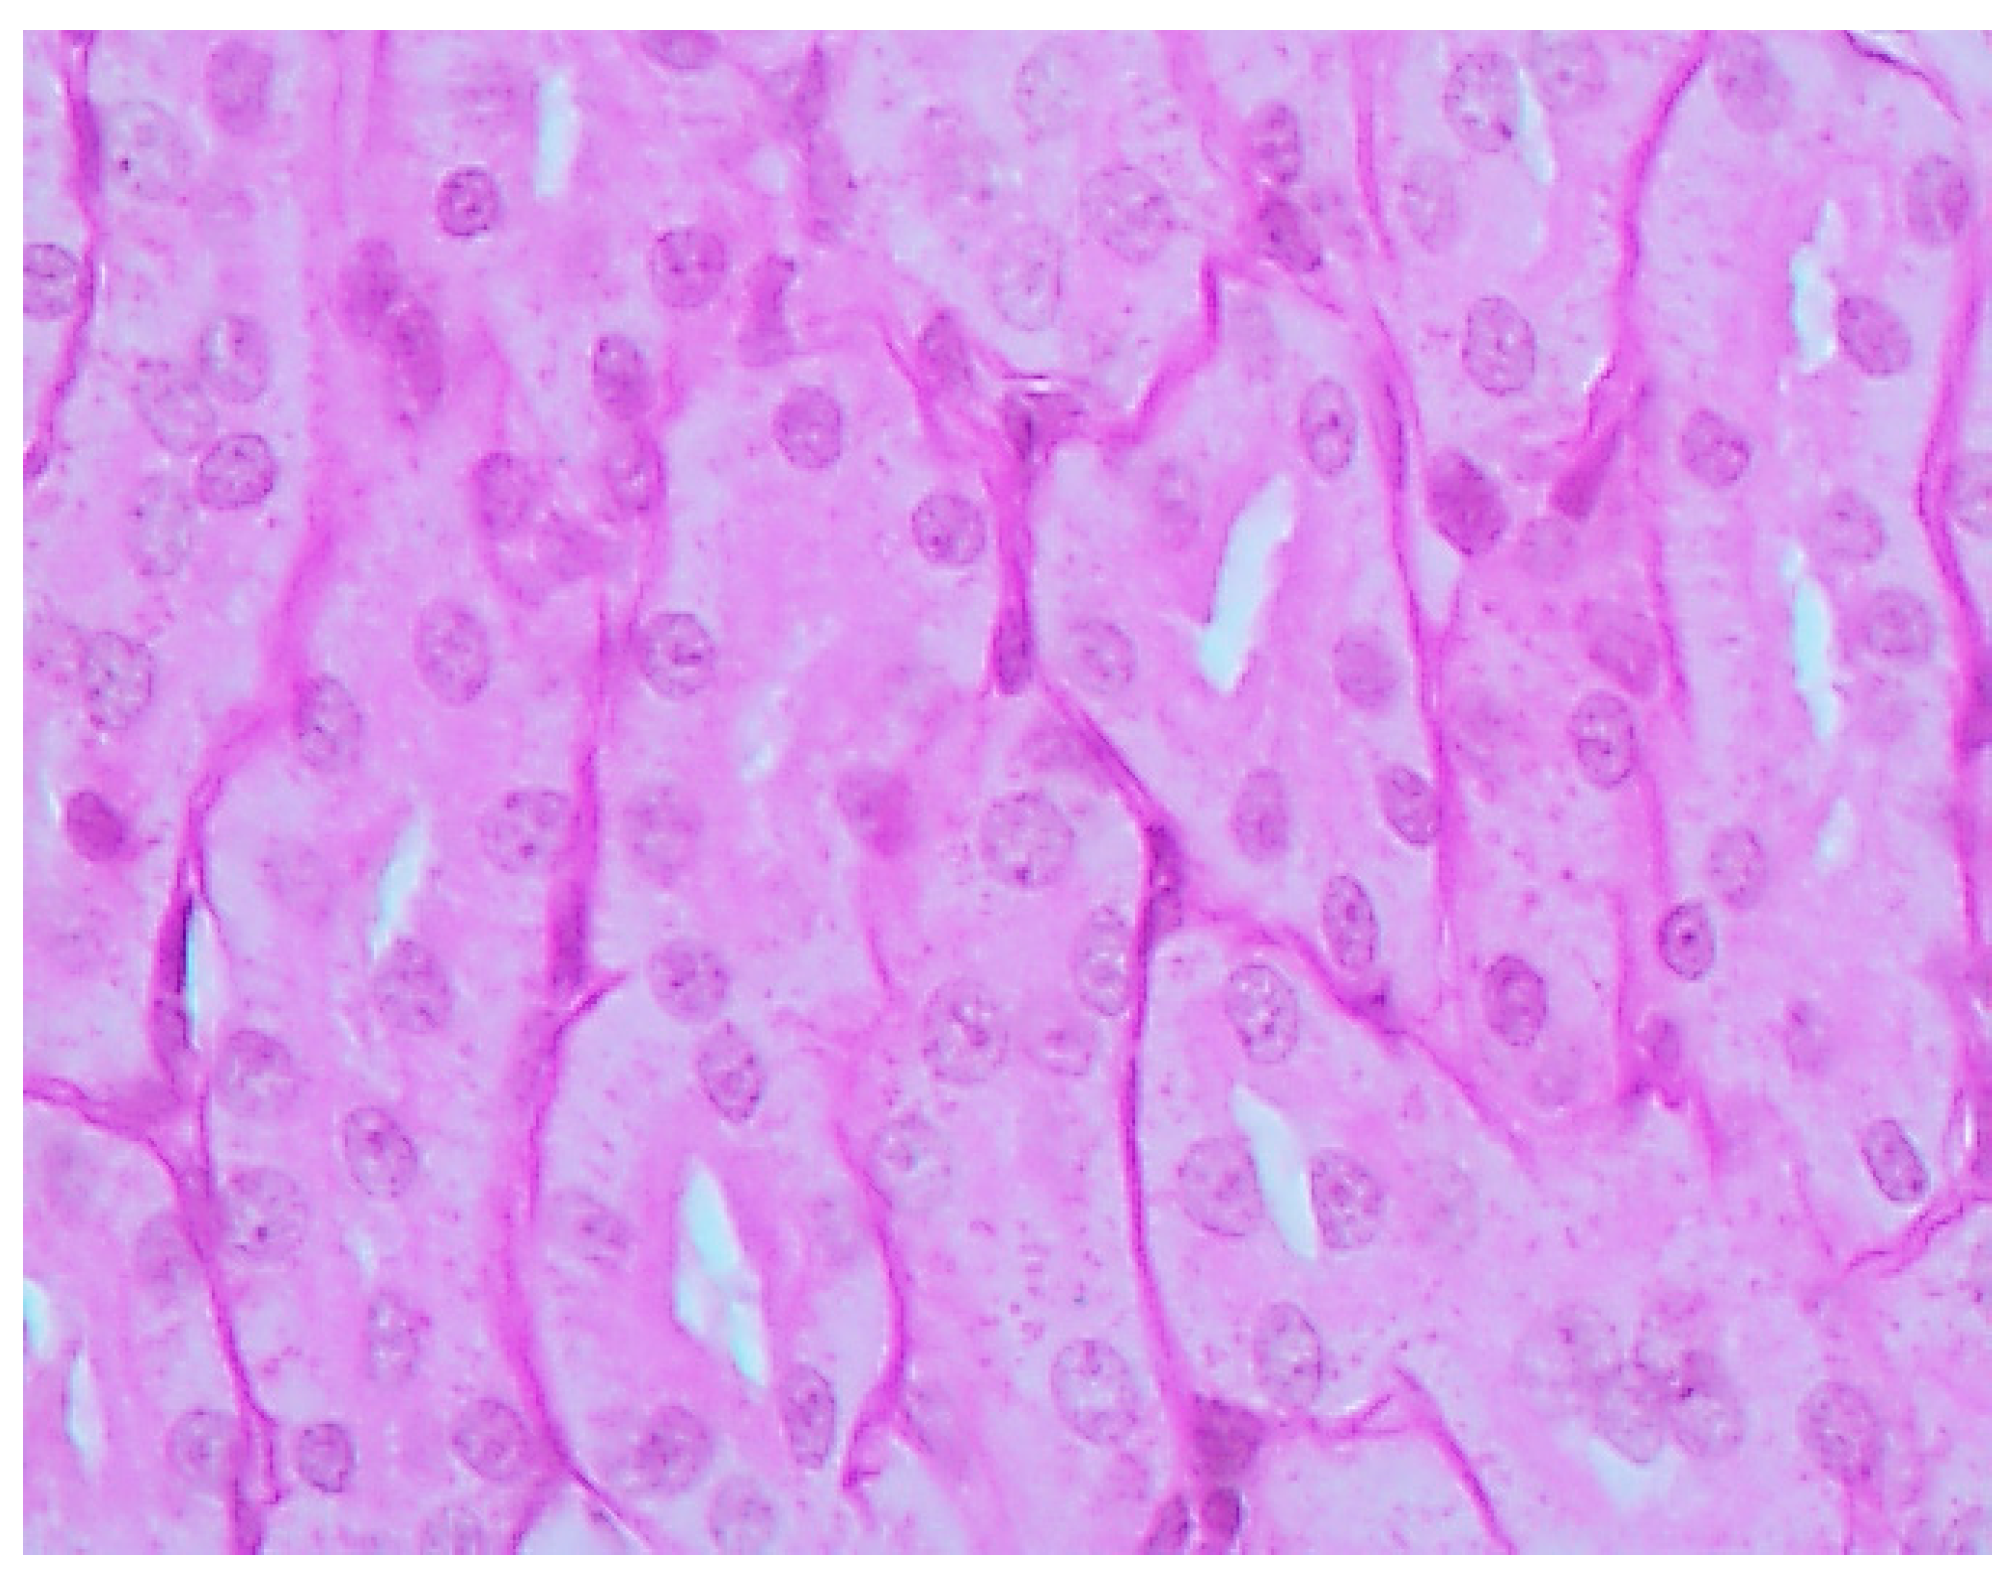

The histological picture (Figure 2, Figure 3 and Figure 4) and morphometric characteristic (Table 4) of the epithelium in the proximal convoluted tubules provide evidence of marked damage, which is a little more marked in response to NiO-NPs and, particularly, Mn3O4-NPs + NiO-NPs, than to Mn3O4-NPs alone, but is absent for the same combined intoxication with the background administration of the BPC.

Figure 2. Kidney of a control rat (proximal convoluted tubules with an intact brush border). Periodic Acid Shiff (PAS) stain, magnification ×400.

Ijms 16 22555 g002